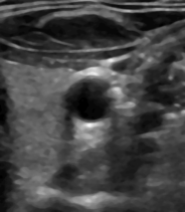

Highly reflective tissue or materials reduce the amount of transmitted sound waves that would pass to tissue more distant to the transducer. This leads to so-called shadowing regions that are particularly prune to noise signals coming from the surrounding tissue. Since sound waves will be dampened while passing through any kind of material, even a body with equal impedance will produce an image with a continuously darker growing shadow. This effect is called downward attenuation and can also be seen in the above images that both get darker in downward direction. An example for shadows can be seen inside the blue coloured circles in the left image.